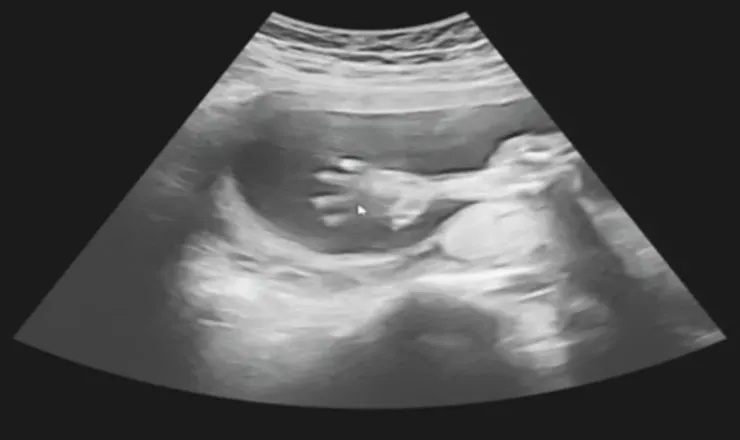

20w+4d活潑的寶寶可以看到手

另外就是情緒價值給好給滿的超音波時間!每次產檢都會先照超音波,醫師都會邊照邊跟寶寶說話,「好好笑喔,很會擺姿勢以後當model喔!」「怎麼不動了呢?快點把手手移開給阿姨看看臉!」然後笑得很開心,我也會郭醫師情緒感染到,聽到醫師跟寶寶講話都會笑出來,醫生形容寶寶的表情跟動作也都很具體,好像在面對真的人,讓我常常好想哭,覺得我肚子裡真的有一個寶寶(本來就有??),這種感覺很難形容,我知道婦產科醫師看過的孕婦跟寶寶非常多,但郭醫師卻還是保有熱情,認真對待我的寶寶。

有次照超音波時寶寶動來動去,郭醫師就很大聲說「欸你今天怎麼那麼high!」然後很開心跟寶寶講話,我老公是個很冷靜且不解風情的理工男,出診間時還跟我說「我覺得醫生比寶寶high欸!」真想翻他個白眼。

可能我太鄉巴佬了,照高層次那天真的滿滿amazing,科技好發達喔!以為照照手指頭、照照器官,想不到是超級精密的照,還可以看到血管、心臟跳動等等,而且是超詳細的照器官!小蛇寶寶算很配合,全程很high動來動去,不過是有點動太快,還看到他搓腳、打哈欠,真的覺得⋯⋯好可愛喔!我已經開始變笨蛋媽媽了嗎?全部大概1小時10分鐘搞定,真是乖孩子。